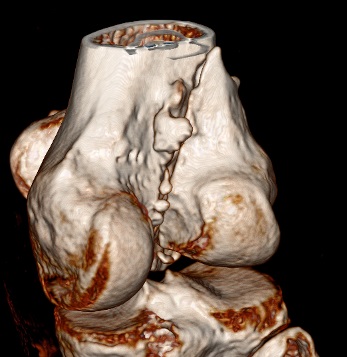

“Перелом наружного мыщелка правого бедра во фрональной плоскости был не замечен”

Диагностическая ошибка происходит, когда игнорируется правила обследования внутрисуставных переломов. Вместо полного обследования, включая КТ, ограничиваются рентгенограммой, и то в одной проекции!

Nork et al, J Orthop Trauma, 87:564, 2005 доложили, что над- и чрезмыщелковые переломы бедра в 38% имеют линию перелома в корональной плоскости!

Спасибо большое за советы! Добавляю некоторые КТ снимки. Перелом коллеги не диагностировали, видимо, расценив костную травму как повреждение задне-латерального комплекса коленного сустава. Отпишусь по результату выполненной операции.